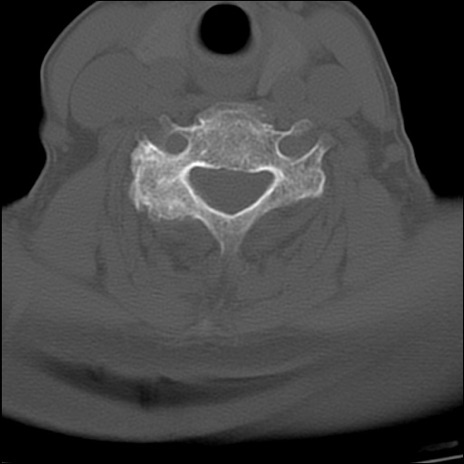

症例48 頚椎CT(横断像)

頚椎CT